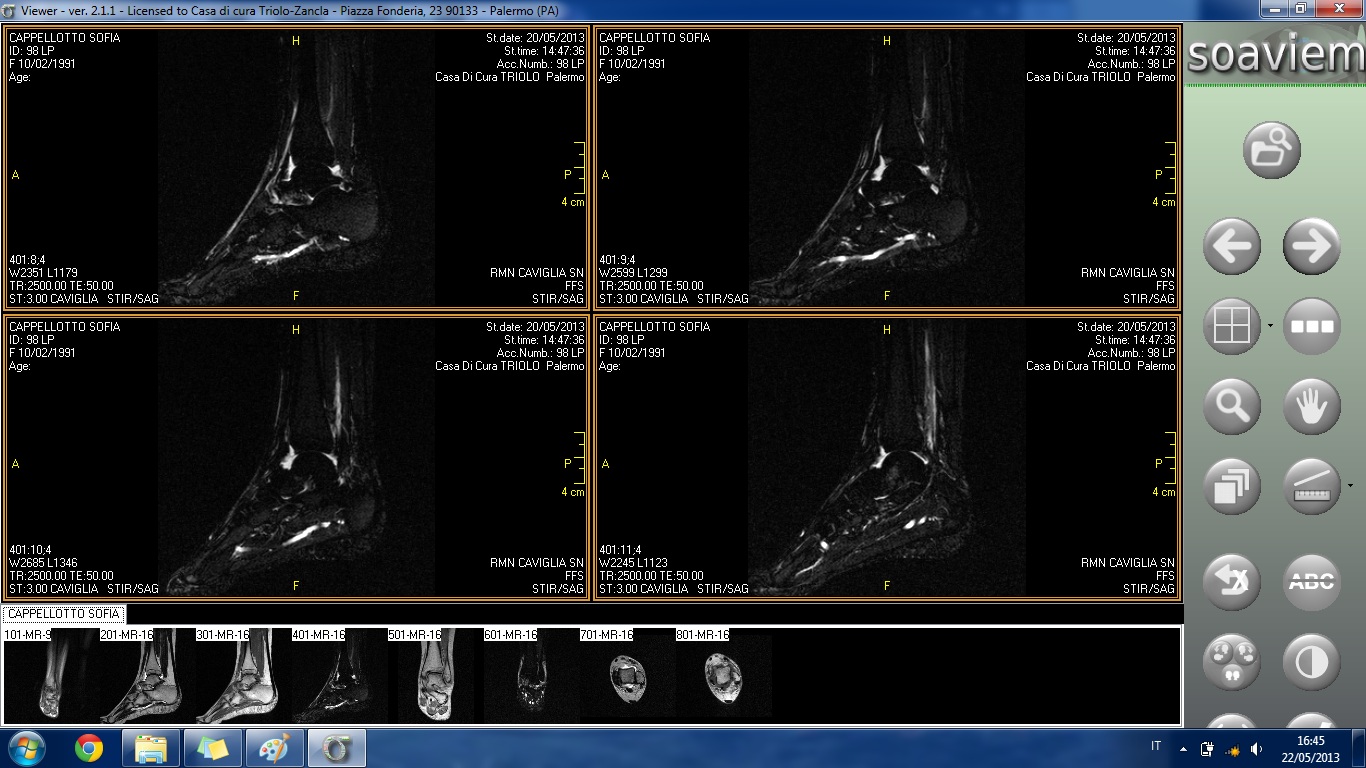

HO FATTO UNA RISONANZA E RIPORTO DI SEGUITO INDICAZIONI TRATTE DAL REFERTO E ALLEGO ALCUNE IMMAGINI:

ESAME ESEGUITO IN TECNICA SE, TSE E STIR MEDIANTE SCANSIONI T1 E T2 PESATE CONDOTTE SUI PIANI ASSIALE, CORONALE E SAGITTALE.

ALTERAZIONE DI SEGNALE DELLA TESTA ASTRAGALICA IN RELAZIONE ALLA PRESENZA DI AREA DI ELEVATO SEGNALE IN STIR DA RIFERIRE AD IPEREMIA TRABECOLARE COME IN ESITI DI IMPATTO OSSEO. REPERTO DI ANALOGHE CARATTERISTICHE DI SEGNALE SI RIVELA A CARICO DEL VERSANTE ANTERIORE DELL'EPIFISI DISTALE DELLA TIBIA ED A CARICO DEL MALLEOLO PERONEALE.

SENSIBILE QUOTA FLUIDA ENDOARTICOLARE.

IL LEGAMENTO PERONEO-ASTRAGALICO ANTERIORE NON APPARE IDENTIFICABILE NELLA PROPRIA CONTINUITÀ ANATOMICA COME PER LESIONE. TUTTAVIA IN RELAZIONE AL RECENTE EPISODIO TRAUMATICO SI CONSIGLIA RIVALUTAZIONE ETG A DISTANZA DI TEMPO. IL LEGAMENTO PERONEO-ASTRAGALICO POSTERIORE ED IL LEGAMENTO DELTOIDEO, SEPPURE INSERITI, MOSTRANO ASPETTO DISOMOGENEO COME PER ESITI DISTRATTIVI.

BEN INSERITO IL LEGAMENTO PERONEO-CALCANEARE.

REGOLARE ASPETTO DEL LEGAMENTO TIBIO-PERONALE INTERNO.

REGOLARE ASPETTO MORFOSTRUTTURALE DEI TENDINI PERONEI E DEI TENDINI DEL COMPARTO ANTERIORE E MEDIALE NEL TRATTO ESPLORATO.

SOSTANZIALMENTE REGOLARE ASPETTO MORFOSTRUTTURALE DEL TENDINE ACHILLEO.

NON SIGNIFICATIVE ALTERAZIONI DEL TROFISMO DEI RESTANTI CAPI SCHELETRICI ESAMINATI.

REGOLARE ASPETTO DELLE STRUTTURE DEL SENO DEL TARSO.